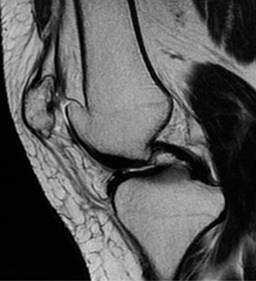

La duplicación patelar es una entidad infrecuente, donde se desarrollan una patela y una patela accesoria a partir de dos núcleos de osificación (Figuras 2 y 3).

Figura 3: Resonancia magnética de rodilla izquierda en secuencia T2 sagital, donde se constata la patela accesoria en disposición medial, con presencia de fibras tendinosas de fijación.